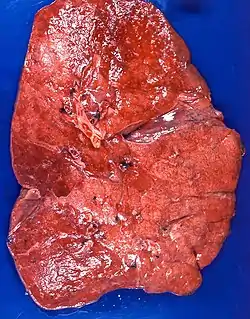

| Lipid pneumonia, exogenous Case 108 | |

Appearance

The gross appearance of a lipid pneumonia is that in which there is an ill-defined, pale yellow area on the lung. This yellow appearance explains the colloquial term "golden" pneumonia.[7]

At the microscopic scale foamy macrophages and giant cells are seen in the airways, and the inflammatory response is visible in the parenchyma.